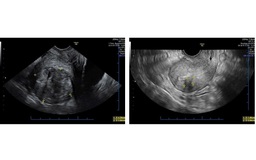

Tại góc nhỏ IVF Center, Bệnh viện Quốc tế City (CIH), những giọt nước mắt và nụ cười hạnh phúc của các cặp đôi hiếm muộn từng tuyệt vọng được đánh thức mỗi ngày. Phía sau phép màu ấy là bác sĩ chuyên khoa 1 Nguyễn Thị Ngọc Sương - người đã lặng lẽ suốt ba thập kỷ đồng hành cùng hành trình tìm con.